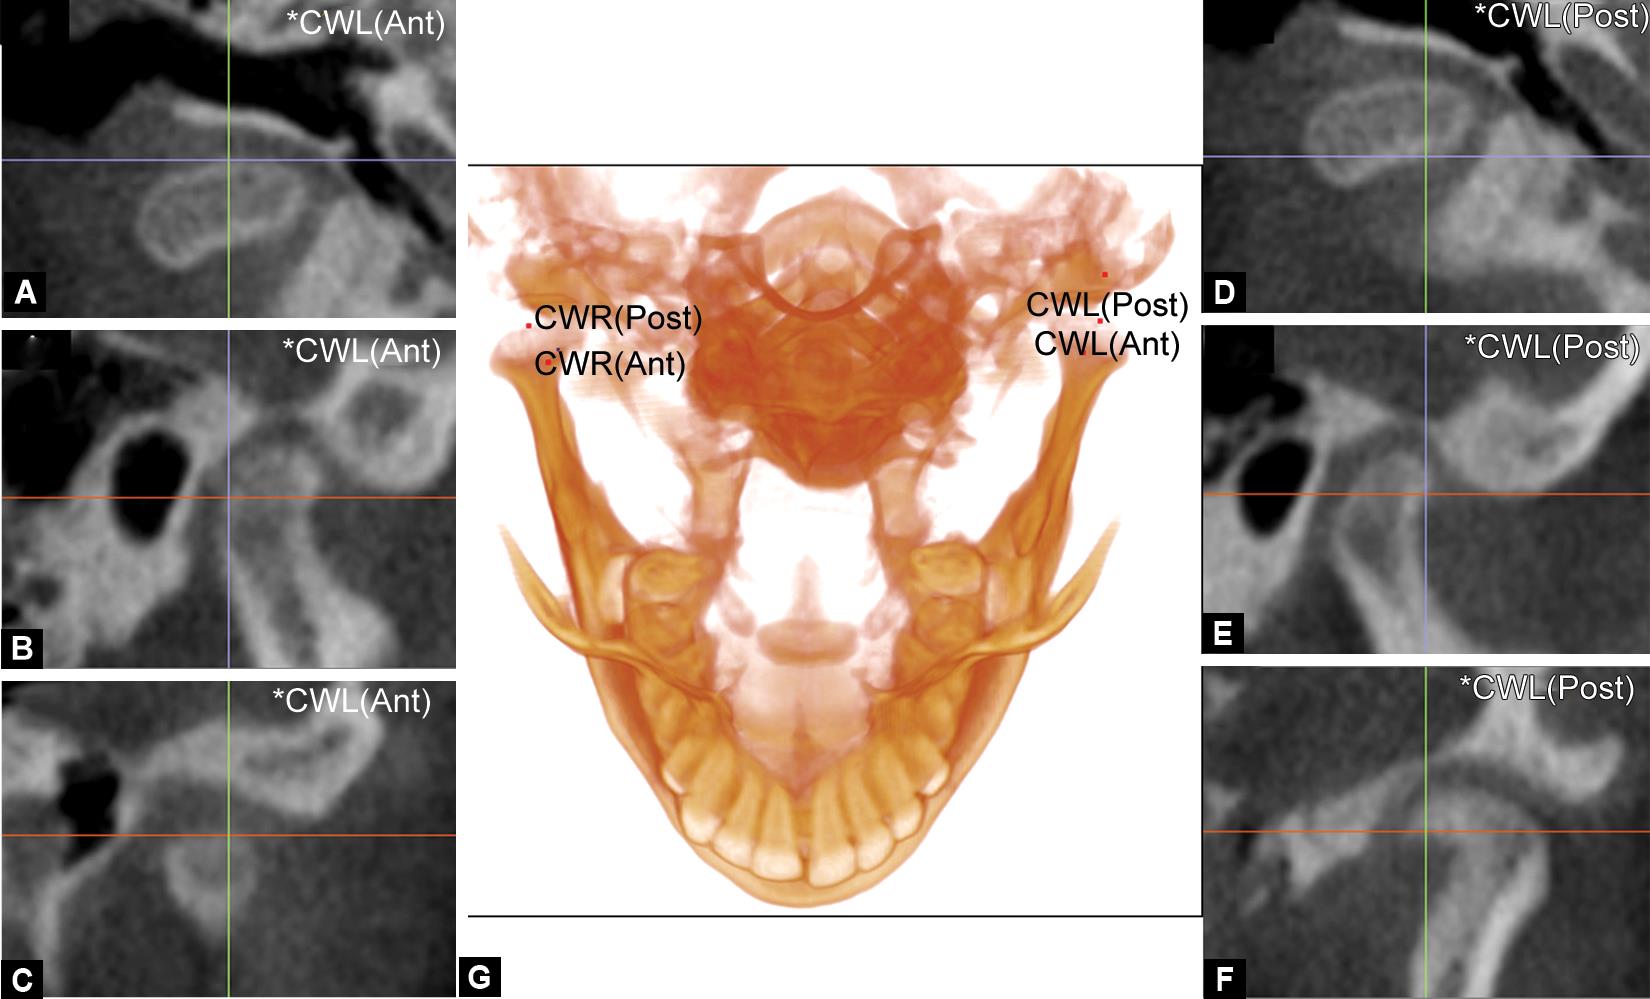

The image analysis was adopted from the 3-D analysis described by Alhammadi et al.20,24 and involved digitizing the different anatomical landmarks included in the analysis on the 3-D volume using slice allocators on the 2-D planes (sagittal, coronal, and axial) (Table 1 and Fig. 1). Three reference planes were used to take the positional measurements:

Figs 1A to G: Digitization of condylar width landmarks on the 3-D volume with the adjustment on the slice locator multiplanar images. The demonstration of the most anterior point of the condyle in (A) axial, (B) sagittal, and (C) coronal planes and the most posterior point of the condyle in (D) axial, (E) sagittal, and (F) coronal planes are represented. The digitization of the most anterior and posterior points of the condyle (G) on the 3D volume is also represented